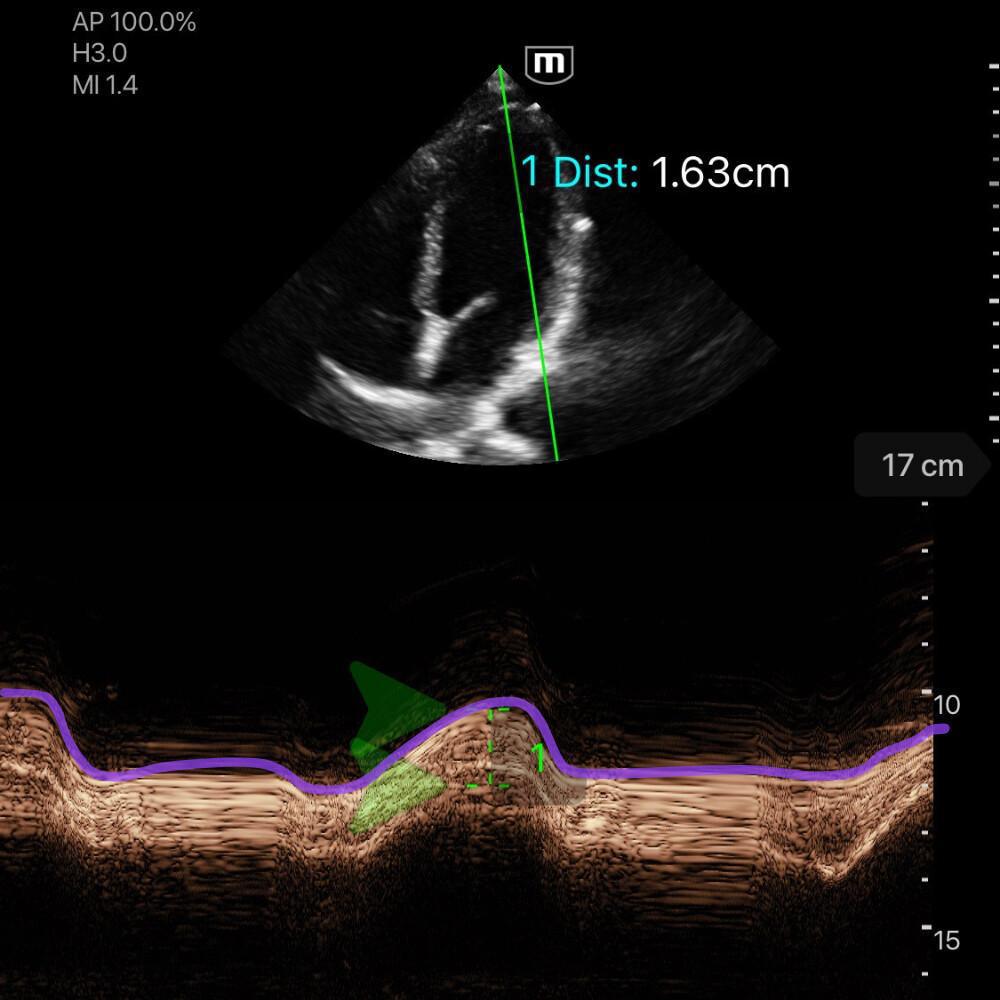

🧮 Calcul MAPSE

Le MAPSE (Mitral Annular Plane Systolic Excursion) mesure le déplacement systolique de l’anneau mitral en mode M.

Le MAPSE est proportionnel à la FEVG : plus le déplacement systolique de l’anneau mitral est faible, plus la fonction systolique du VG est réduite.

Comment mesurer le MAPSE

-

Vue apicale 4 cavités.

Placez le mode M sur l’anneau mitral latéral, ou médial (séptal).

Mesurez la hauteur de l'onde correspondante au mouvement systolique vertical, entre la base de la ligne et le pic (cf. photo ci-dessous, ligne violet).

Interprétation

MAPSE < 8 mm → altération significative de la FEVG

MAPSE 8–10 mm → fonction modérément diminuée

MAPSE > 10 mm → fonction systolique conservée